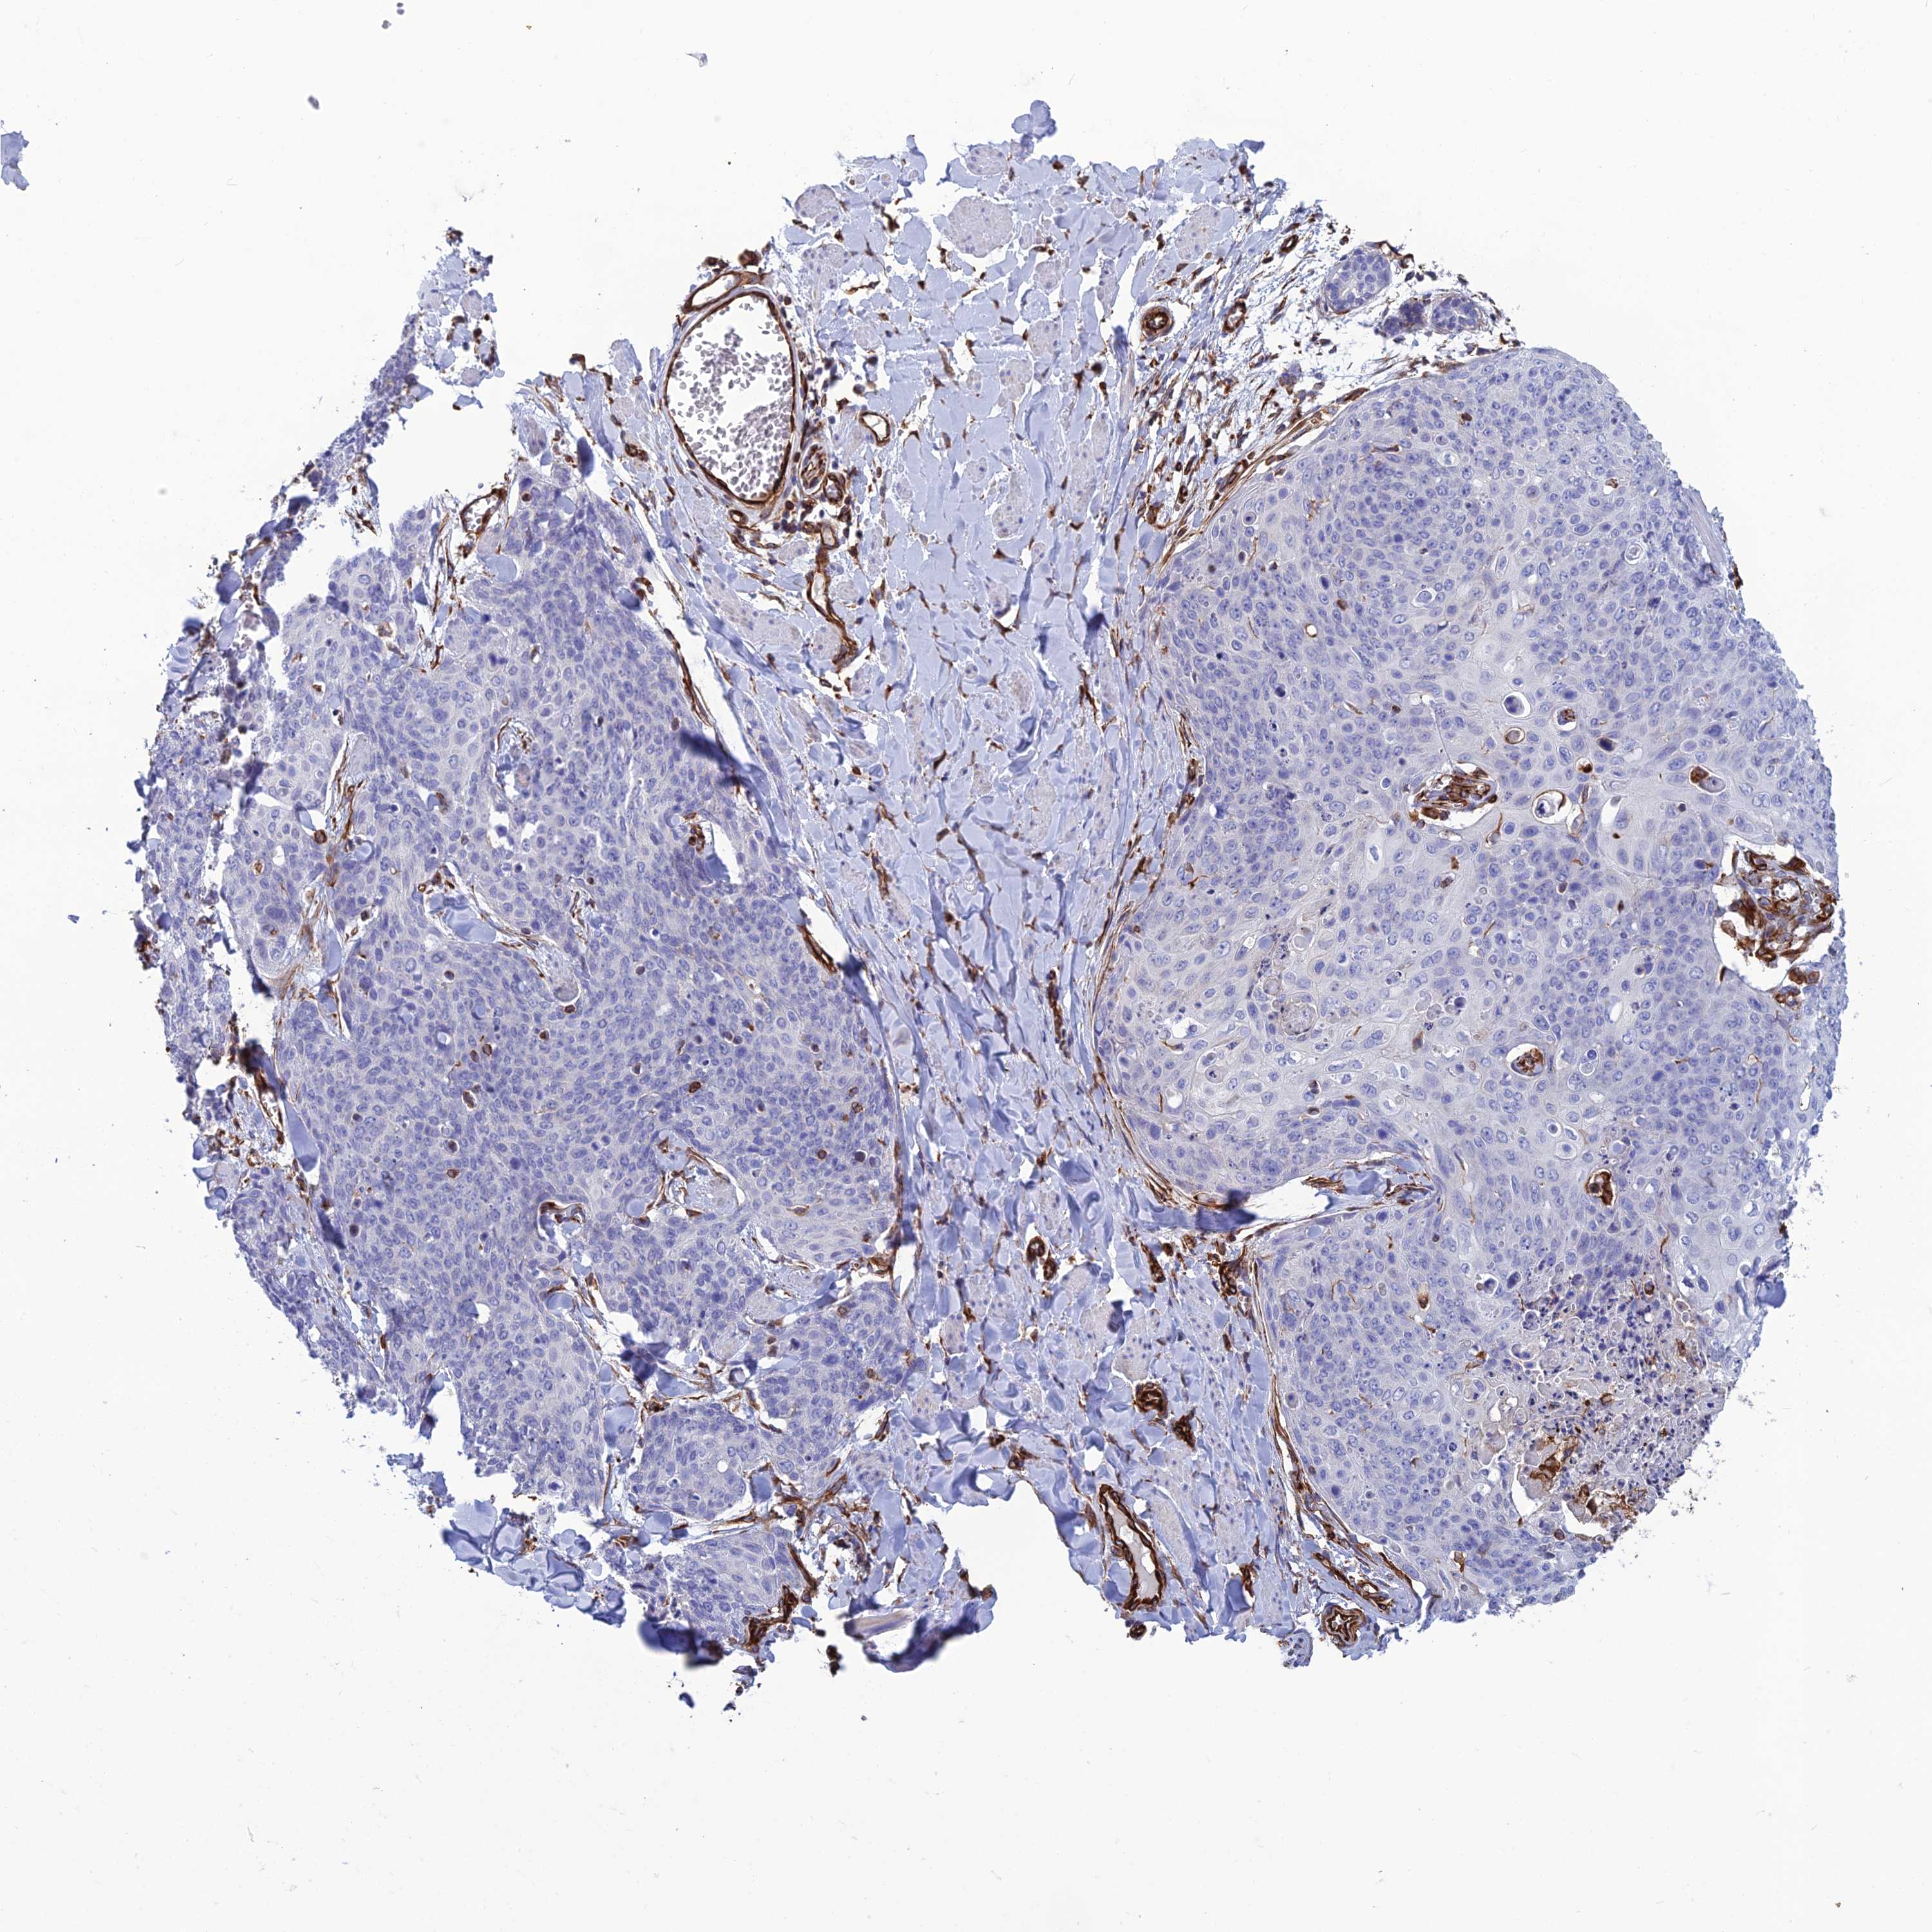

CANCER SKIN CANCER Show tissue menu

Basal cell and squamous cell cancer

SKIN CANCER - Protein expressioni

A mouse-over function shows sample information and annotation data. Click on an image to view it in a full screen mode. Samples can be filtered based on level of antibody staining by selecting one or several of the following categories: high, medium, low and not detected. The assay and annotation is described here.

Each image is clickable and will lead to virtual microscopy that enables deeper exploration of all samples and also displays staining intensity scores, fraction scores and subcellular localization as well as patient and tissue information for each sample.

Antibody HPA044748

Antibody HPA050397

Basal cell carcinoma

Squamous cell carcinoma, NOS

Squamous cell carcinoma, metastatic, NOS